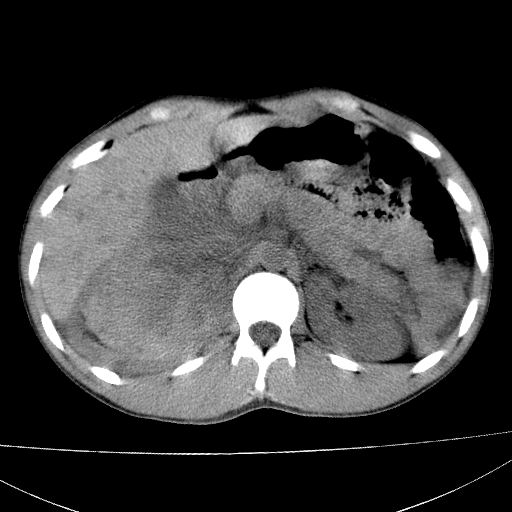

标题: CT15860:男,21岁,腹部外伤2小时伴胸疼。 [打印本页]

标题: CT15860:男,21岁,腹部外伤2小时伴胸疼。

b超示:肝破裂。

肝脏及肾脏明显有损伤性改变并激发腹腔内积液(血),以肝脏撕裂及肾周积血显著。

1)肝破裂伴腹腔积液(血)。2)右肾破裂伴右肾包膜下及肾周血肿。3)腹部空腔脏器穿孔可能。4)右侧少量胸腔积液(血)。

1)肝破裂伴腹腔积液(血)。2)右肾破裂伴右肾包膜下及肾周血肿。3)右侧少量胸腔积液(血)。

肝、右肾包膜下血肿,右侧腰大肌及腹膜后血肿;腹腔少量积血;腹腔疑有少量游离气体伴肠破裂。

1肝挫伤伴腹腔积液。2右肾挫裂伤伴右肾包膜及肾后间隙肿血肿。3右肾脏周围的积气,十二指肠显示结构不清,考虑十二指肠降部破裂可能性大。